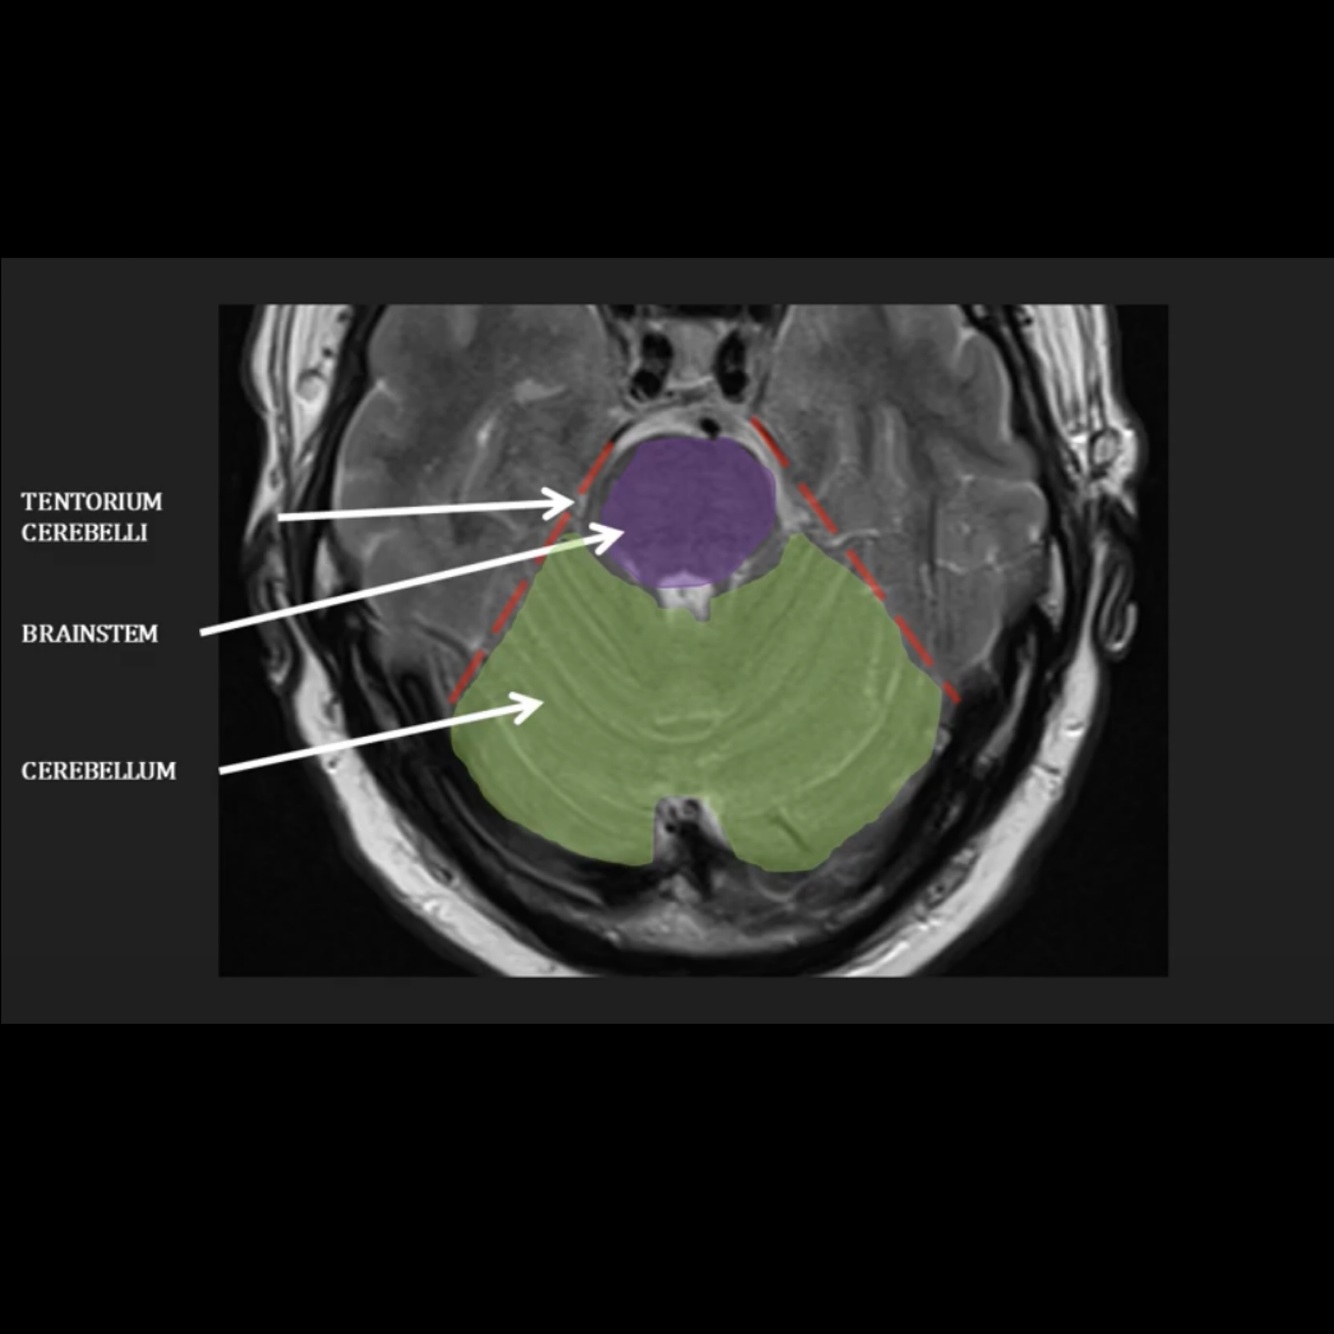

Q

Which structure is filled with CSF and surrounds the brainstem and what is it called, and which structure is the fourth ventricle?

) basal cistern